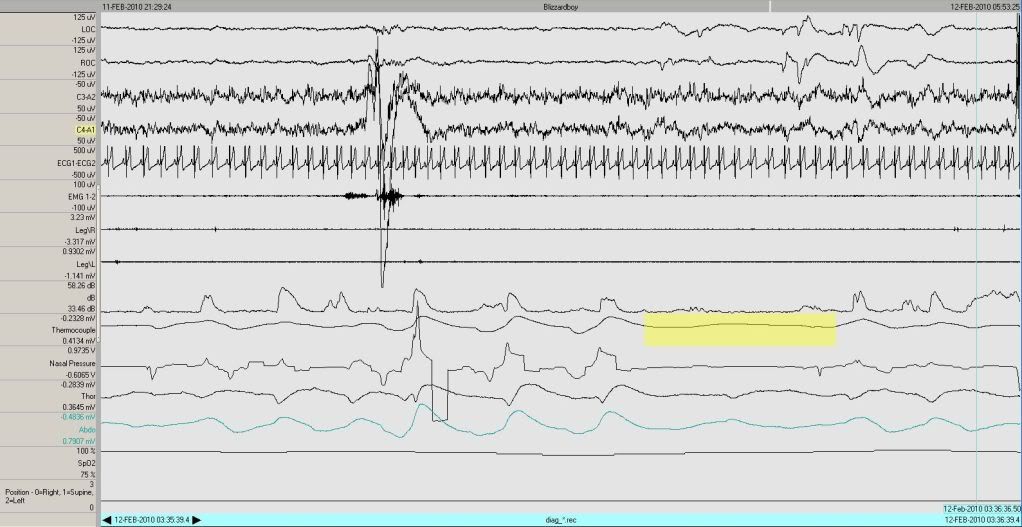

Oh, right, REM.

Everybody wants to see REM.

So there's bbREM:

Image